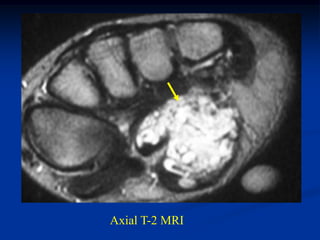

Case #270.2           Axial T-1             T-2

Gad

56 year male with painless soft

mass in anterior thigh for 2 years